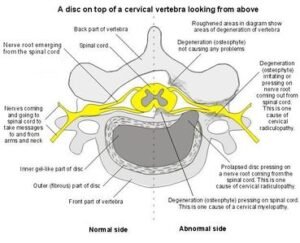

Шиповете във врата, известни още като костни шипове (остеофити), представляват костни образувания, които се развиват по ръбовете на прешлените в шийната част на гръбначния стълб.

С течение на времето организмът може да образува костна тъкан като реакция на нестабилност или натоварване, което води до появата на остеофити.

• наличие на костни образувания (остеофити)

• дегенеративни промени в прешлените

• намаляване на пространството между прешлените

• притискане на нервни структури

• стесняване на междупрешленните отвори

• дискова херния във врата

• шийна радикулопатия